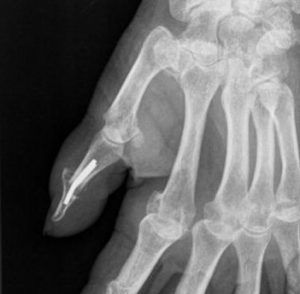

A destruição articular geralmente provoca luxação ou sub-luxação da articulação com erosão da base de F2 e afunilamento da extremidade distal de F1.

O tratamento está limitado à fixação cirúrgica da articulação (Artrodese). Estas artrodese podem ser feitas de várias formas.

Figuras 30 e 31: Luxação IF; artrodese articular